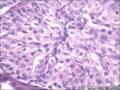

卵巢里边这两团是什么、?巧克力囊肿吗?伴黄体血肿吗?组织中的腺体是子宫内膜腺体吗

• 卵巢里边这两团是什么、?巧克力囊肿吗?伴黄体血肿吗?组织中的腺体是子宫内膜腺体吗图1

图1

图1-5,Brenner细胞巢。6,黄体,是不是血肿,要看多大吧。7-10是子宫内膜异位囊肿。11,确定也是卵巢吗?

图1-5,Brenner细胞巢。